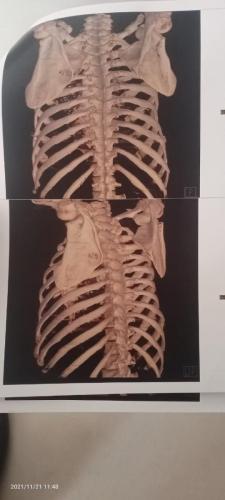

Photo Gallery Dr. Monika Gupta - Photo Gallery 7 5 2 8 6 Dr. Atul Kumar Gupta - Photo Gallery « ‹ of 3 › » Video Gallery